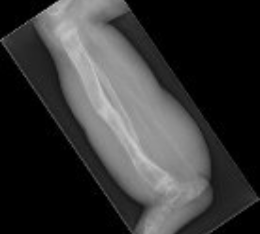

X-rays show a severe tibial deformity corrected with a Taylor Spatial frame.